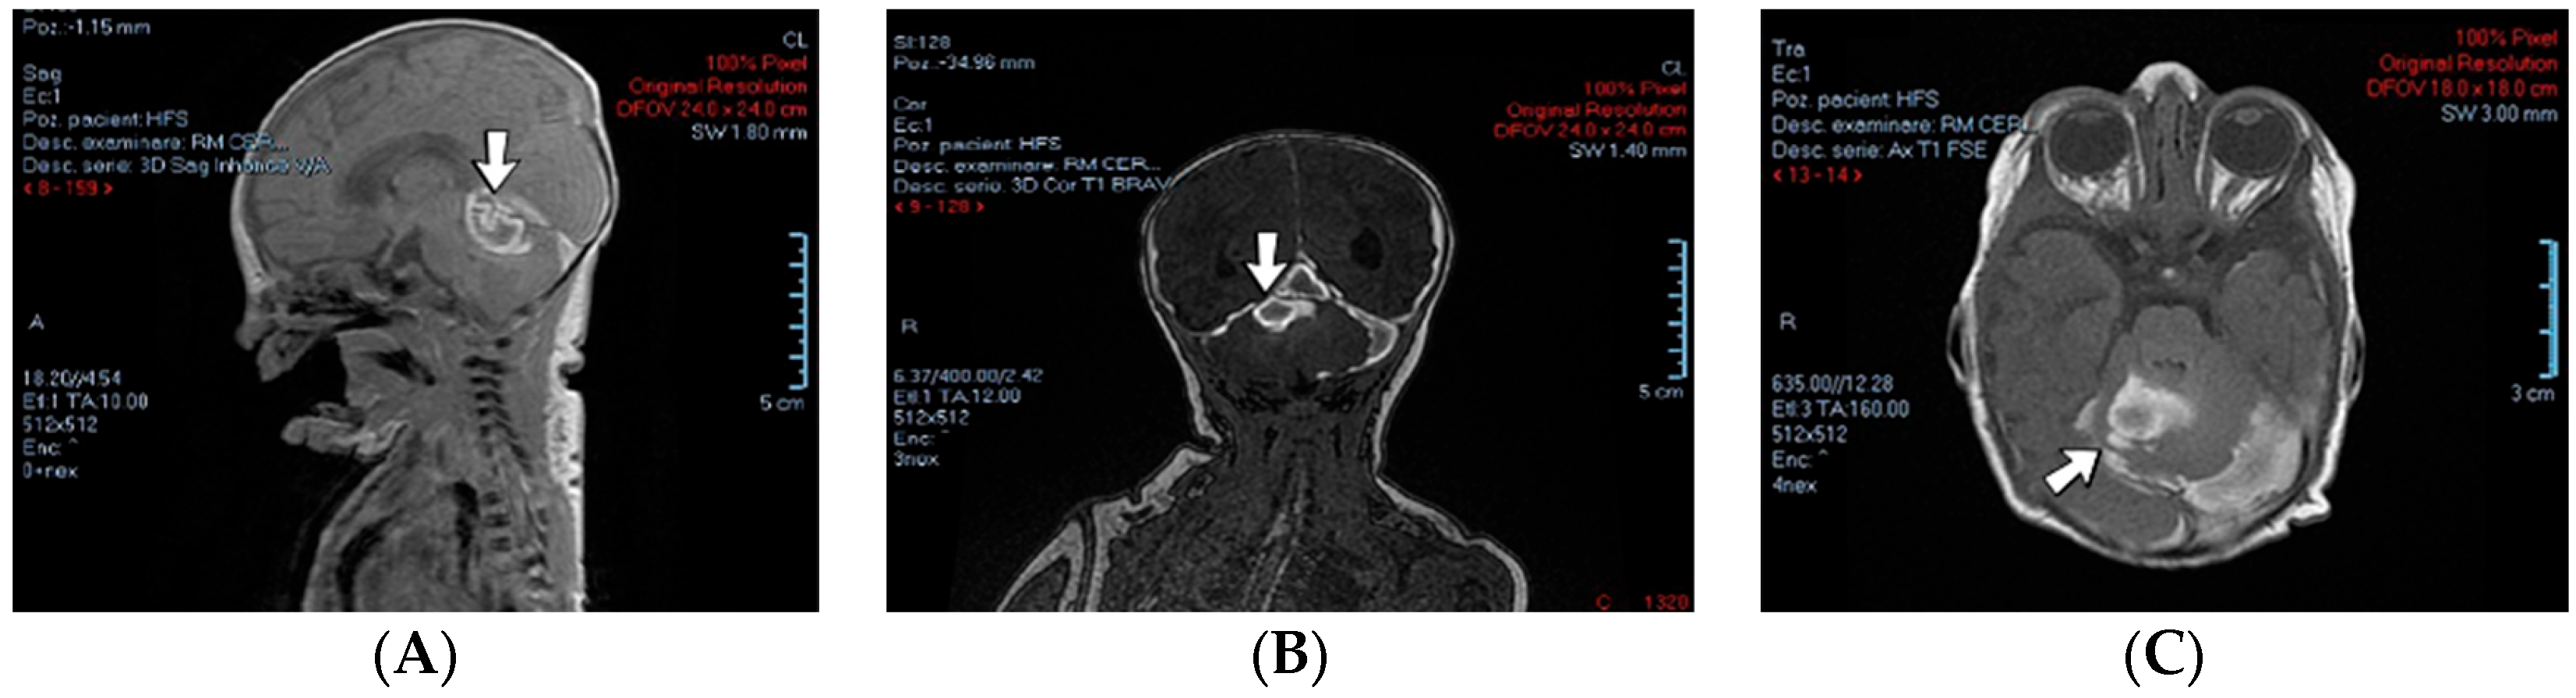

4.15. Case No. 15—Postnatal Posterior Cranial Fossa Hemorrhage, Subarachnoid Hemorrhage, Thrombosis of the Right Transverse and Sigmoid Cerebral Venous Sinuses, Hydrocephalus

A 4-day-old female neonate (40 weeks, 3.10 kg) presented signs of increased intracranial pressure: projectile vomiting, bulging anterior fontanelle, and spasticity. The patient had previously developed seizures at 8 h of life, treated with phenobarbital. The first ultrasound of the brain performed at birth was normal; the second one performed at 3 days of life showed hydrocephalus of the lateral ventricles. A brain CT scan performed at 3 days of life identified right pericerebellar hemorrhage in the posterior cranial fossa, causing stenosis of the Sylvius aqueduct, hydrocephalus, and subarachnoid hemorrhage of the right temporal lobe, tentorium cerebelli, quadrigeminal, and ambiens cisterns of the brain (Figure 6). The laboratory findings from birth and 3 days of life showed leukocytosis.

Figure 6.

Case no. 15. Posterior cranial fossa hemorrhage on brain MRI—sagittal (A), frontal (B), and transverse (C) views.

The admission laboratory findings showed elevated procalcitonin. Two RT-PCR tests for SARS-CoV-2 infection were performed with negative results due to a positive maternal infection before birth. Later, a brain MRI performed at 7 days of life showed thrombosis of the right transverse and sigmoid cerebral venous sinuses and mild hydrocephalus of the lateral ventricles. A suspicion of right internal jugular vein thrombosis and elevated D-dimer tests led to the initiation of treatment with enoxaparin.

Genetic testing confirmed inherited thrombophilia, with a positive MTHFR C677T homozygous gene mutation and Protein C deficiency. Normal homocysteine and PAI-1 levels were detected. There was a positive maternal history of three miscarriages and oligohydramnios during pregnancy.